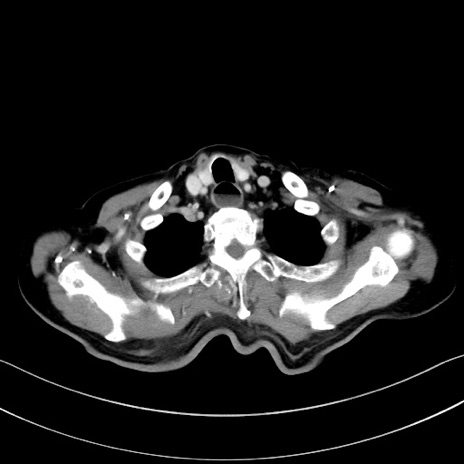

症例28(横断像)

【症例】60歳代男性

【主訴】嘔吐

【現病歴】胃癌にて胃全摘後。食思不振が悪化し、夜中に嘔吐することがある。

【既往歴】胃癌、胃全摘、脾摘、胆摘後

【データ】WBC 5900、CRP 10.56